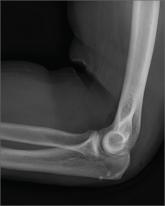

A Different Source of Elbow Pain

- Author:

- Nandan Hichkad, PA-C, MMSc

Publish date: August 2, 2013